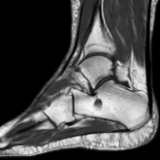

A patient presents with pain in the sole of the foot on both sides, especially on the left side, which occurs with exertion, particularly during the first steps in the morning.

The question of whether there are rheumatic manifestations or whether the complaints are mechanically induced should be clarified.

Mild plantar fasciitis and intraosseous ganglion of the calcaneus